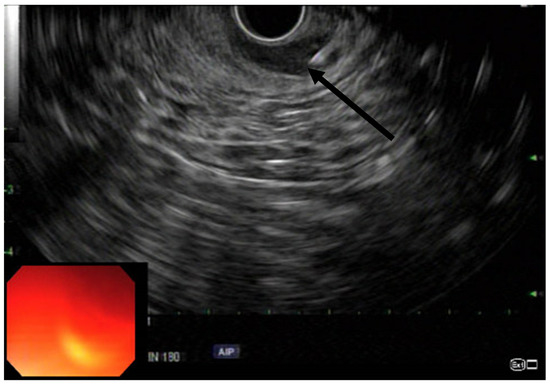

EUS was performed using a linear array echoendoscope (Figure 1, Figure 2 and Figure 3). Eighty units of type A botulinum neurotoxin was diluted in 2 cc of isotonic saline. An echoendoscope was introduced into the anal canal. The internal sphincter was identified sonographically and a 25-gauge needle was introduced into the internal sphincter. Then, 0.5 cc of saline-containing 20IU BTX was injected into the internal sphincter. The needle was withdrawn, the scope was rotated 90 degrees and the second injection was given. This process was repeated for a total of 4 times giving 0.5 cc per quadrant. Conscious sedation or MAC anesthesia was used for the procedure.

Figure 1. Radial EUS with arrow pointing to IAS.